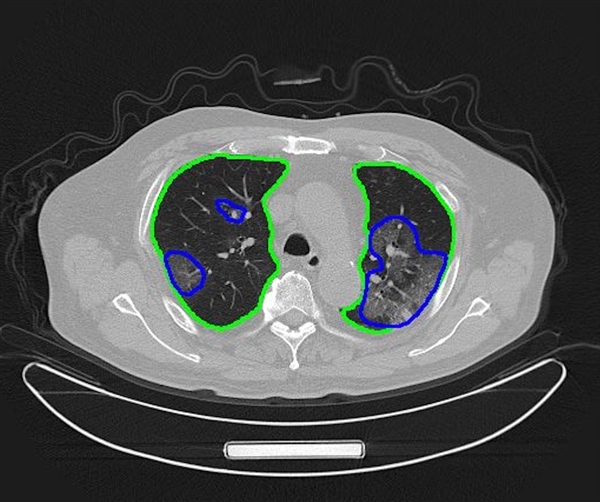

面对大量新冠肺炎病人的诊断需求,腾讯拿出搭载最新“腾讯觅影”AI的应急专用CT装备,支援湖北前线医院,最快2秒就能完成AI模式识别,1分钟内即可为医生提供辅助诊断参考。

AI对CT图像进行自动分割:绿色圈为肺部,蓝色圈为新冠肺炎病灶